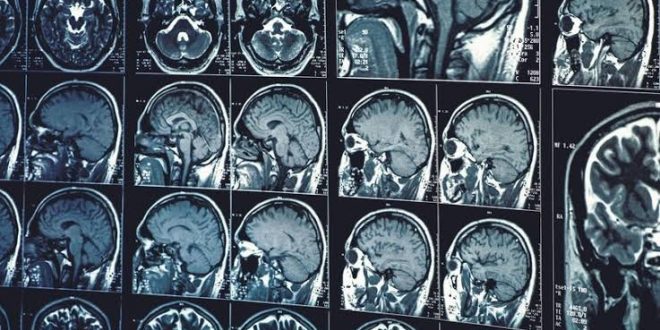

Hastalık, beyinde ödeme neden olabiliyor

Yetkililerin açıklamasında, 2022’de sadece bir kişinin hastalığa yakalandığının tespit edildiği, virüsün bulaştığı kişilerin çoğunda hastalık belirtisi olmadığı ancak hastalığın beyinde ödem oluşturabileceği bilgisi yer aldı.